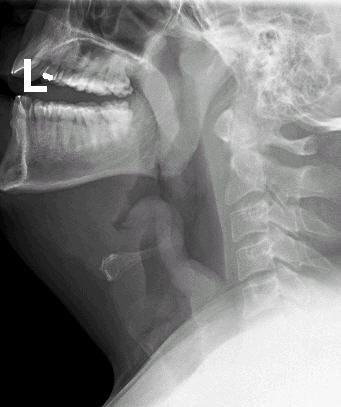

ეპიგლოტიტის პირდაპირი ვიზუალიზაცია (უნდა ჩატარდეს მხოლოდ საოპერაციოში მართული სიტუაციის პირობებში, სასუნთქი გზების დახშობის შემთხვევაში დაუყოვნებელი ინტუბაციისათვის) ან კისრის ლატერალური/გვერდით პროექციაში რენტგენოგრაფიით.[Figure caption and citation for the preceding image starts]: ლატერალურ პროექციაში კისრის გამოსახულება, რომელზეც ეპიგლოტიტი ისახებადოქტორ პეტრის პერსონალური კოლექციიდან; გამოყენებულია თანხმობით [Citation ends].